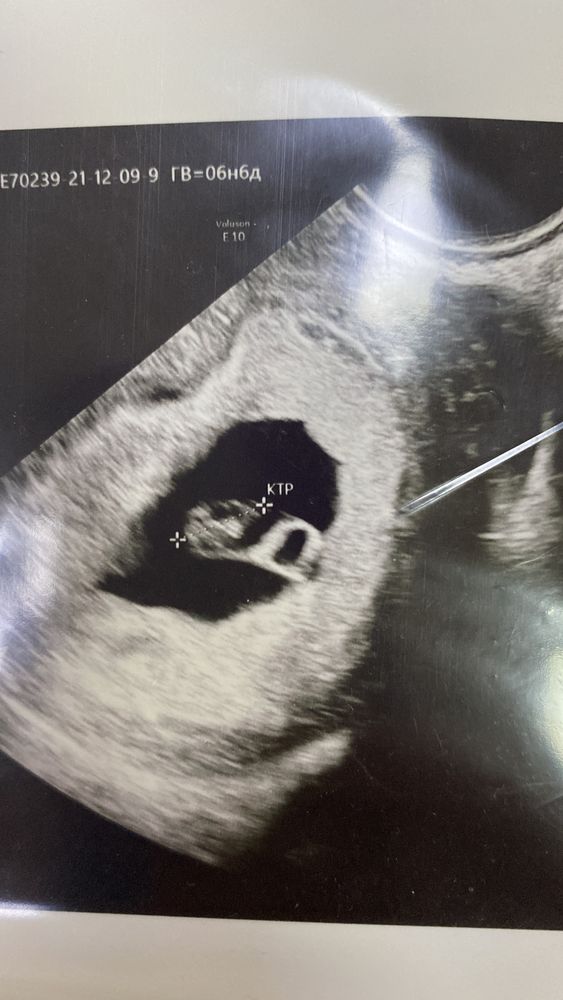

7 недель , встала на учёт

Елена, сразу на дюфастон перевели , больше утрик не ставлю, а так да, выходил бы и дальше бежевым. У меня уже две недели бежевое всё внутри, гематома по узи, увеличили дюфастон + магний+папаверин…завтра капельницу ещё какую-то поставят, по узи с малышкой всё хорошо даже опережает